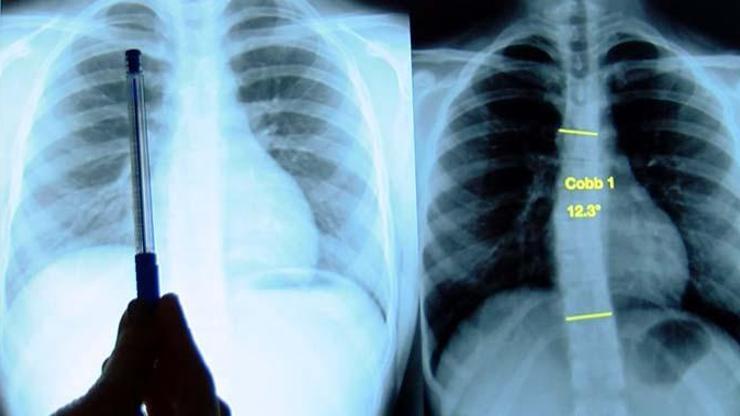

'Ayakta çekilen röntgen filmi ve muayene ile anlaşılır'

Normal ve sağlıklı omurgada omurların arkadan bakıldığında yukarıdan aşağıya, boyun, sırt ve bel bölgelerinde düz bir hat şeklinde uzandığına dikkat çeken Prof. Dr. Özgür Özdemir, "Skolyozda ise omurlar sağa veya sola doğru yer değiştirir, aynı zamanda kendi eksenleri etrafında döner. Omurgaya arkadan bakıldığında eğrilik düz durulduğunda bile fark edilebildiği gibi, bazen bu denli net değildir ve ancak öne eğilme durumunda, kontroller ve röntgen filmlerinde anlaşılabilir" dedi.

Omuz seviyeleri arasında eşitsizlik, bel çukurlarındaki asimetri, bel kemiğinde bir tarafın öne çıkıntı yapması, sırtta bir tarafta kemik kabarıklığı (kürek kemiğinde tümsek görünümü), vücut dengesinde sağa ya da sola kaymanın skolyoz belirtisi olduğunu vurgulayan Prof. Dr. Özgür Özdemir, hastalığın tanısının, ayakta çekilen tüm omurgayı içine alan röntgen filmi ve klinik muayene ile yapıldığını kaydetti.